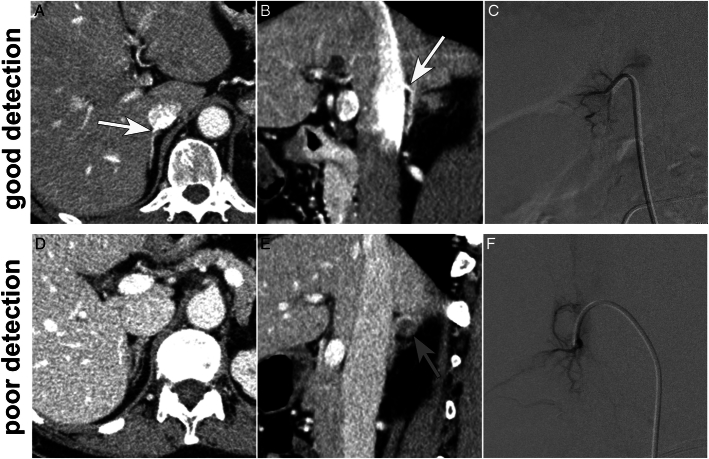

Results: The qualitative detectability of RAV was deemed good in 15 patients and poor in 21 patients. Regression analysis revealed that only heterogeneous enhancement of inferior vena cava with bolus high attenuation, corresponding to an optimal acquisition timing from time-intensity curve analysis, was associated with a good detectability of RAV (odds ratio, 5.06). The use of HRCT was not statistically significant.

Conclusions: Optimal acquisition timing is a crucial factor for the detectability of RAV in preprocedural CT for AVS, while high-resolution 0.25 detector CT appears to have limited significance.